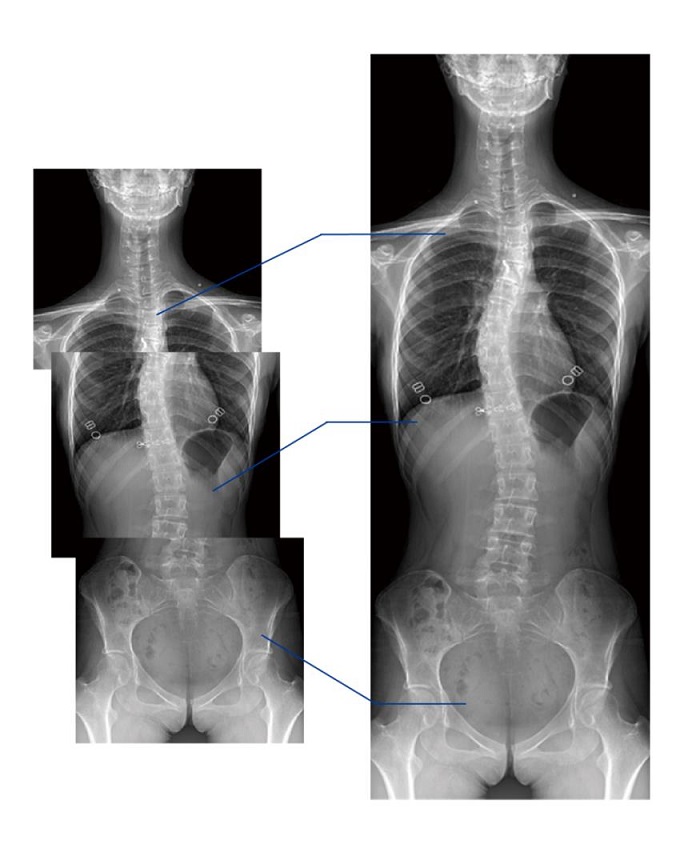

隱匿性骨折高清圖像

另外,動態DR的全景拼接功能,可通過對脊柱、下肢及下肢靜脈造影進行分段攝片,然后對分段圖像進行拼接,在一幅X光圖像上完整顯示全脊柱或下肢整體形態。對于骨科疾病患者的全脊柱、全下肢病變情況圖像展示更加具有完整性,有助于骨科疾病患者臨床診斷效果的提升。